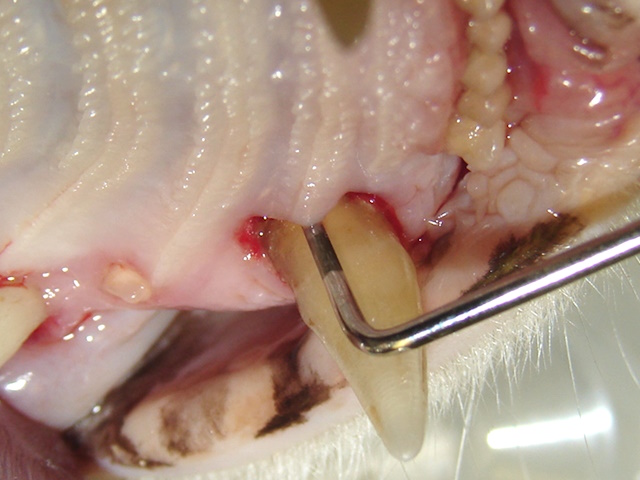

Significant periodontal disease around mandibular canines and incisors presenting with deep pockets, gum recession and tooth mobility.

Maxillary canine tooth of this cat appears extruded due to chronic periodontal disease. The tooth appears longer than normal with a significant amount of root exposure.

Deep periodontal pocket on the palatal surface of the upper canine.